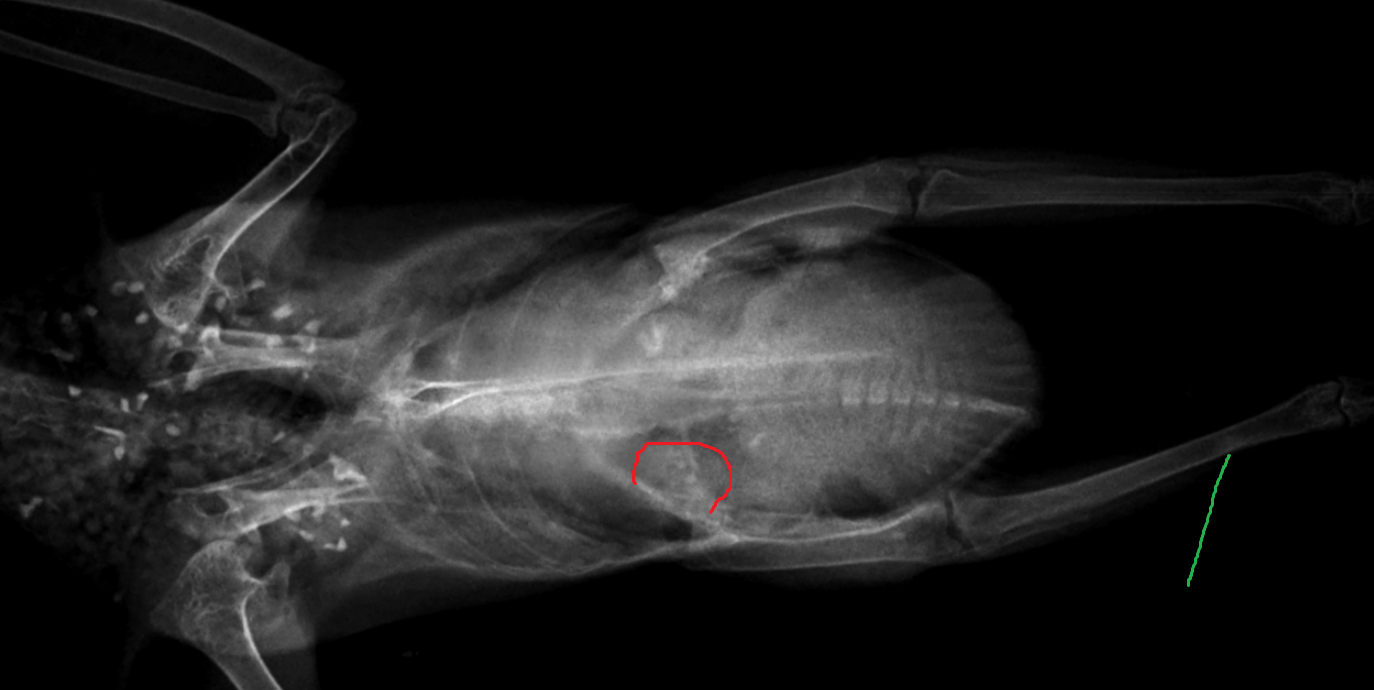

Deem Опубликовано 30 сентября, 2024 Автор #379 Опубликовано 30 сентября, 2024 Сегодня желчь пошла, но помёта практически нет – в основном вода. Продолжаю колоть Глюкозу, Кальция глюконат. Дексаметазон пока колоть не буду, это – на крайний случай т.к. средство иммунодепрессивное, а голубка и так слаба; вколю если вдруг вчерашний приступ повторится. 22 часа назад, маленький принц сказал: 22 часа назад, ната1805 сказал: @Deem Живот сейчас не увеличен у голубки? живот у птиц между килем и попой Вот её живот: Помёт за ночь: Помёт днём:

Deem Опубликовано 3 октября, 2024 Автор #380 Опубликовано 3 октября, 2024 (изменено) @маленький принц @Ильяна @ната1805 @Zosia @Анна1972 @Физкульт-привет! @Cabrera Вчера сделали рентген голубке в городе. Если всё пойдёт хорошо, сегодня выложу снимки, но качество у них не очень – делал не специалист. После вчерашней 4-х часовой поездки на общественном транспорте (в первой клинике не оказалось цифрового рентгена, пришлось ехать ещё дальше), Пятачку стало хуже: у неё очень болит правая сторона, она даже правое крыло голубка держит более опущенным и на правую лапу совсем не сановится – держит её немного назад и в бок, на весу; помёта сегодня вообще небыло, хотя вчера худо-бедно но пара крошечных кучек с водой была; сейчас стоит нахохлившись, есть даже не пытается, хотя вчера утром немного ковырялась в просо. Утром осмотрел её живот ещё раз: всётаки у голубки живот больше чем у голубя, и правая сторона её живота увеличена, по сравнению с левой... Вес голубки упал до 235 грамм... Изменено 3 октября, 2024 пользователем Deem

Deem Опубликовано 3 октября, 2024 Автор #383 Опубликовано 3 октября, 2024 (изменено) @маленький принц @Ильяна @ната1805 @Zosia @Анна1972 @Физкульт-привет! @Cabrera Это несколько сжатые конверсии в ".png", т.к. форум не принимает ".dcm" медицинского стандарта DICOM. Изменено 3 октября, 2024 пользователем Deem

Deem Опубликовано 3 октября, 2024 Автор #384 Опубликовано 3 октября, 2024 (изменено) Совсем плохо голубке: ходить почти не может, на жёрдочку запрыгнуть тоже, иногда заваливается на правую сторону, помёта весь день нет – всего несколько маленьких лужиц мутной грязно-жёлтой слизи с уратами... По глазам видно, что ей очень больно; не знаю как ей помочь... что делать? Изменено 3 октября, 2024 пользователем Deem